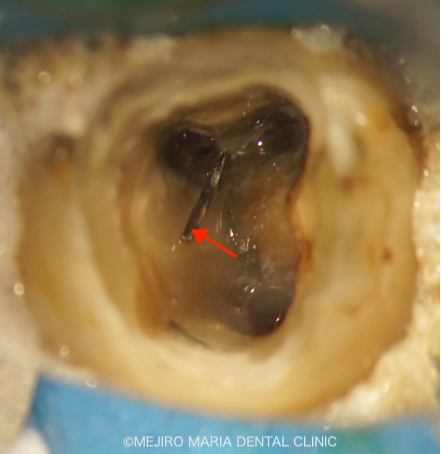

今回の治療はまず、上部の築造体にあるスクリュータイプ(写真1:赤矢印)の除去、ならびに、近心根にある破折ファイル(写真1:黄色矢印)の除去が、治療の際に手間となる工程でした。

築造体や破折ファイルの除去の際に、虫歯を除去するような回転切削器具を無闇に使用すると、余分な歯質を削ってしまい、歯の強度を著しく失う原因や、穿孔(パーフォレーション/穴が開くこと)という偶発事故を起こしたりする危険性が高くなります。そのため、回転切削器具の使用は最小限に抑え、専用の超音波ファイルを用いて除去するのが、理想的な治療であると考えます。

適切な箇所で、適切な器具を選択することが、非常に重要となります。

超音波ファイルを使用し、無事にファイルを除去した後は、通法通りの根管治療を行いました。下記の動画もご参照ください。